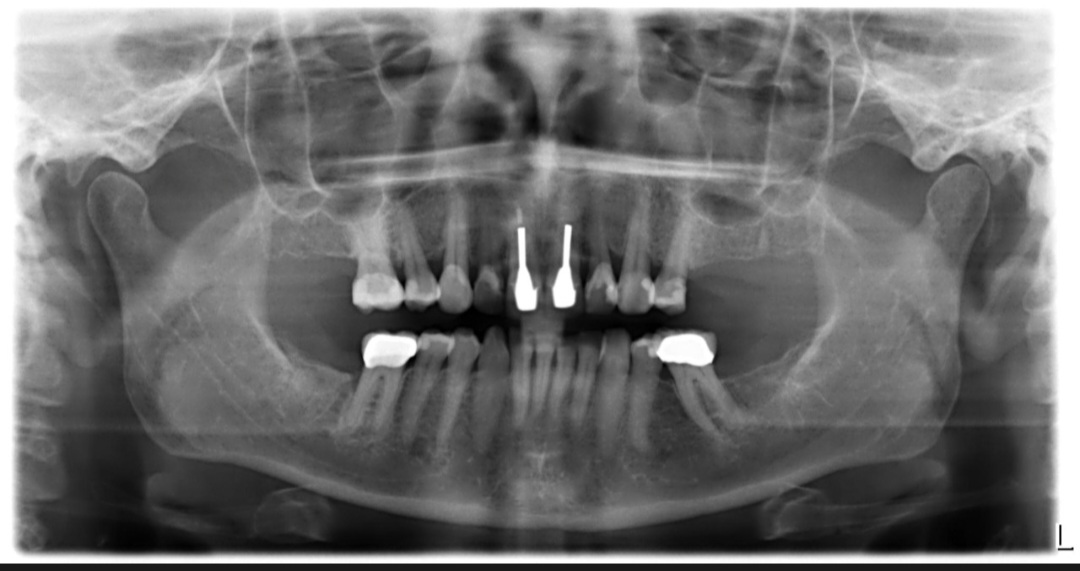

Beste Tandarts Richard, hier de rontgenfoto.

Gaat mij niet om herkenbaarheid, ging mij om schaamte over mijn eigen gebit.

Maar vind uw mening belangrijk hierover, dus ik ga hem toch plaatsen.

Dankjewel alvast.

---"Eerst de ophanging in orde door de parodontoloog, niet mondhygiënist . De parodontoloog heeft dan de verantwoording en zal de hulp v d mondhygiënist gebruiken. Als ik de foto bekijk denk ik dat u rechts voldoende stabiliteit heeft maar links boven net een kies tekort komt. Is het echt nodig meer kiezen te maken u heeft nu het minimale noodzakelijke. Flink botafbraak in het front boven en oppassen bij de 46/16. Of de boven front op den lange duur te behouden is hangt af van wat de parodontoloog kan bereiken. Belangrijker hoe goed u uw gebit kunt verzorgen. Rookt of heeft u in het verleden gerookt... dat zou voor mij veel verklaren. Als u bereid bent een uitneembare voorziening, zoals een frame te dragen, dan heeft u zelfs voldoende aan de 23/24 en de 13/14 om een frame aan op te hangen mits die elementen gezond zijn, ( parodontoloog) de voortanden kunnen mooi in de frame opgenomen worden na eventuele extractie. Bereid om de ankers v e frame prothese te accepteren dan hoeven die 4 elementen niet bekroond te worden, behalve misschien de 14/24 afhankelijk v d grootte v d vullingen. Anders kunnen voorzieningen in die 4 kronen gemaakt worden om de functie v d ankers over te nemen. Er zijn ook alternatieven afhankelijk v uw budget. Indien voldoende bot aanwezig en parodontaal gezond, niet rokend, zou u ook ter vervanging v d 4 front elementen twee implantaten en een 4 delig implantaat gedragen brug kunnen plaatsen etc etc ...verschillende alternatieven maar allemaal afhankelijk v hoe goed U vooral en de parodontoloog de fundering rustig kunnen krijgen. Verschillende zienswijzen/oplossingen afhankelijk v d behandelaar."---